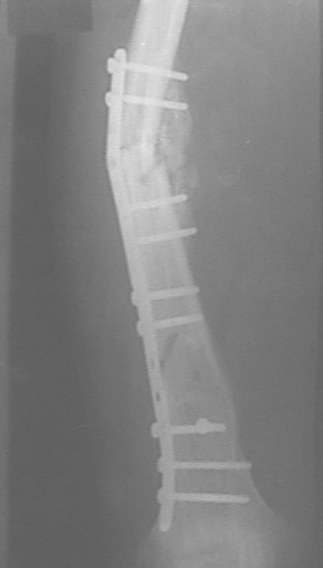

Александр Николаевич, к сожалению больной не является на контрольные осмотры. Я последний раз видел больного, когда прошло 7 месяцев после операции БОС. У него все хорошо. Каких либо жалоб и ограничений в нагрузке нет. Высылаю снимки до операции и последние снимки.